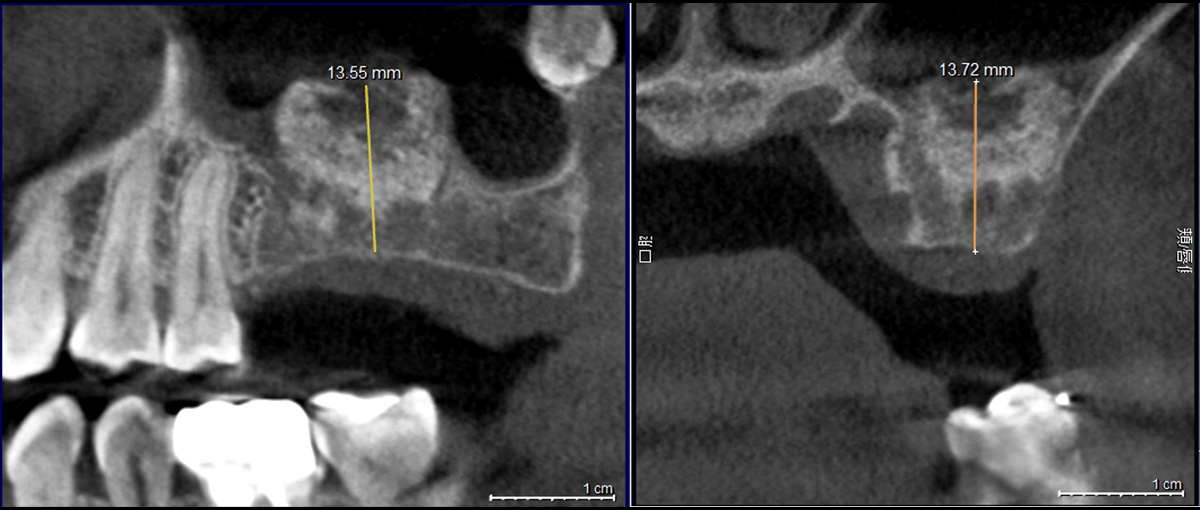

【サイナスリフト後レントゲン写真】

上顎洞(副鼻腔)の下に骨造成材(Bio-Oss)を填入し、インプラントを支えるために十分な骨の厚みを確保しています。

治療前と比べ、黒く抜けていた部分が白く写っており、新しく骨が作られていることが確認できます。